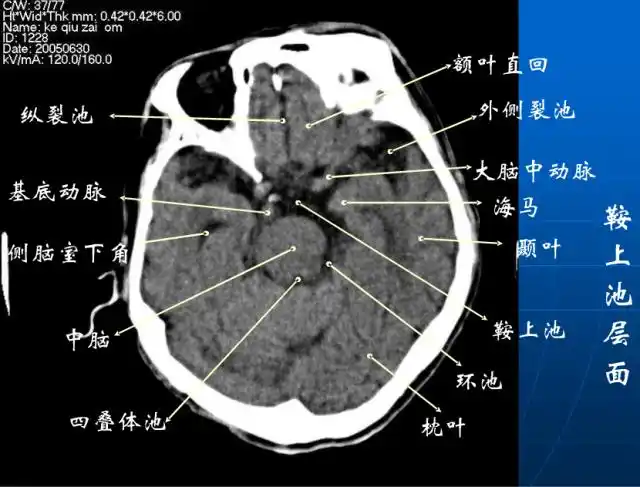

头颅ct解剖与常见出血梗死判读